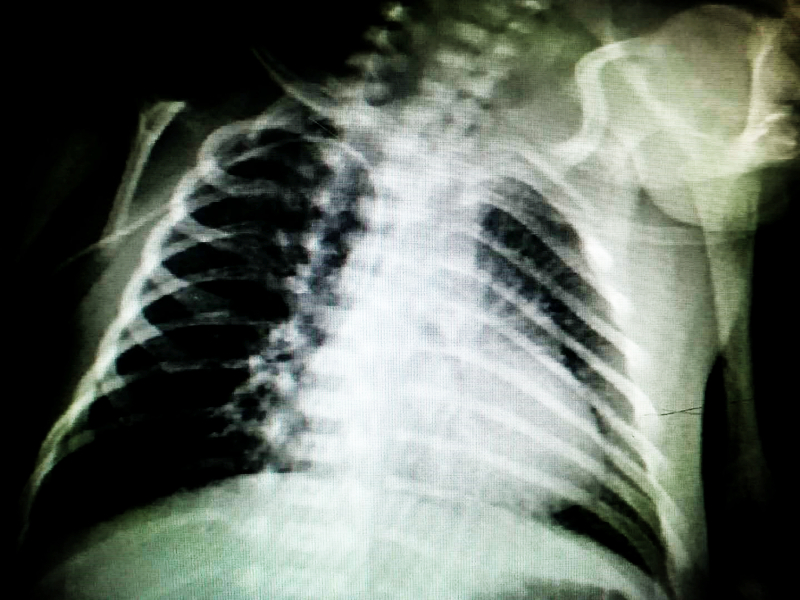

5月30日14:00,在护士长苏秀蓉帮助支持下,新生儿专科护士蔡寅秀、王雪在详细了解患儿病例资料,充分评估患儿病情和血管条件下,对该名患儿进行了PICC置管。术中选取右侧贵要静脉为最佳穿刺,沿静脉走行达上腔静脉并通过拍片确定导管尖端位于上腔静脉,穿刺过程顺利,患儿无特殊不适。